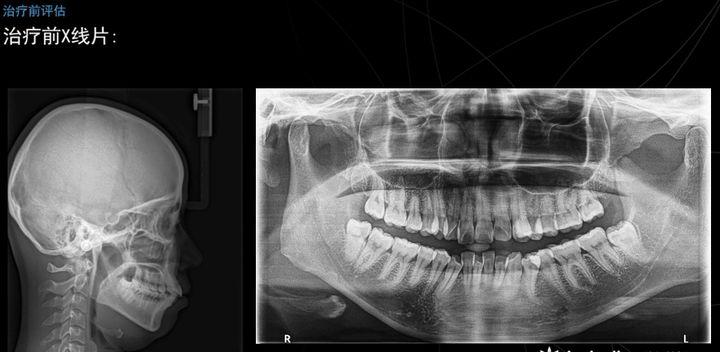

下图是他的头颅定位测位片和全颌曲面断层片,可以看到髁突的一个大概形态以及头颅,侧帽,软组织,牙齿的一个关系。

这是我们进行一个头影测量的描记,几个简单数据的记录,她的ANB角是4.8度,轻度的骨性二类的患者,她的下颌平面角是33度,是均角型的,她的下颌形态也比较好,基本接近偏平长方形。

头影测量的数据,比较异常的就是这个ANB角,我们诊断她是属于一个安氏一类,骨性二类,深覆合深覆盖牙列拥挤,上下颌骨存在一个失状向不调。我们觉得她失状向不调,可能上颌前突的程度要占据更多的一个因素。

可以看到她矫正后的头颅定位测位片和全额曲面断层片,侧貌可以看到她的突度已经的改良了许多,髁肌紧张也大大缓解了不少,可以看到调节前ANB为4.5,调节后变成3.8,下颌平面角也由33度变成32.5度,上颌前牙的角度也相应改变,虽然变化的度数不是特别大,但是能看到她的外貌上面是柔和了很多,突度也有了的改良。